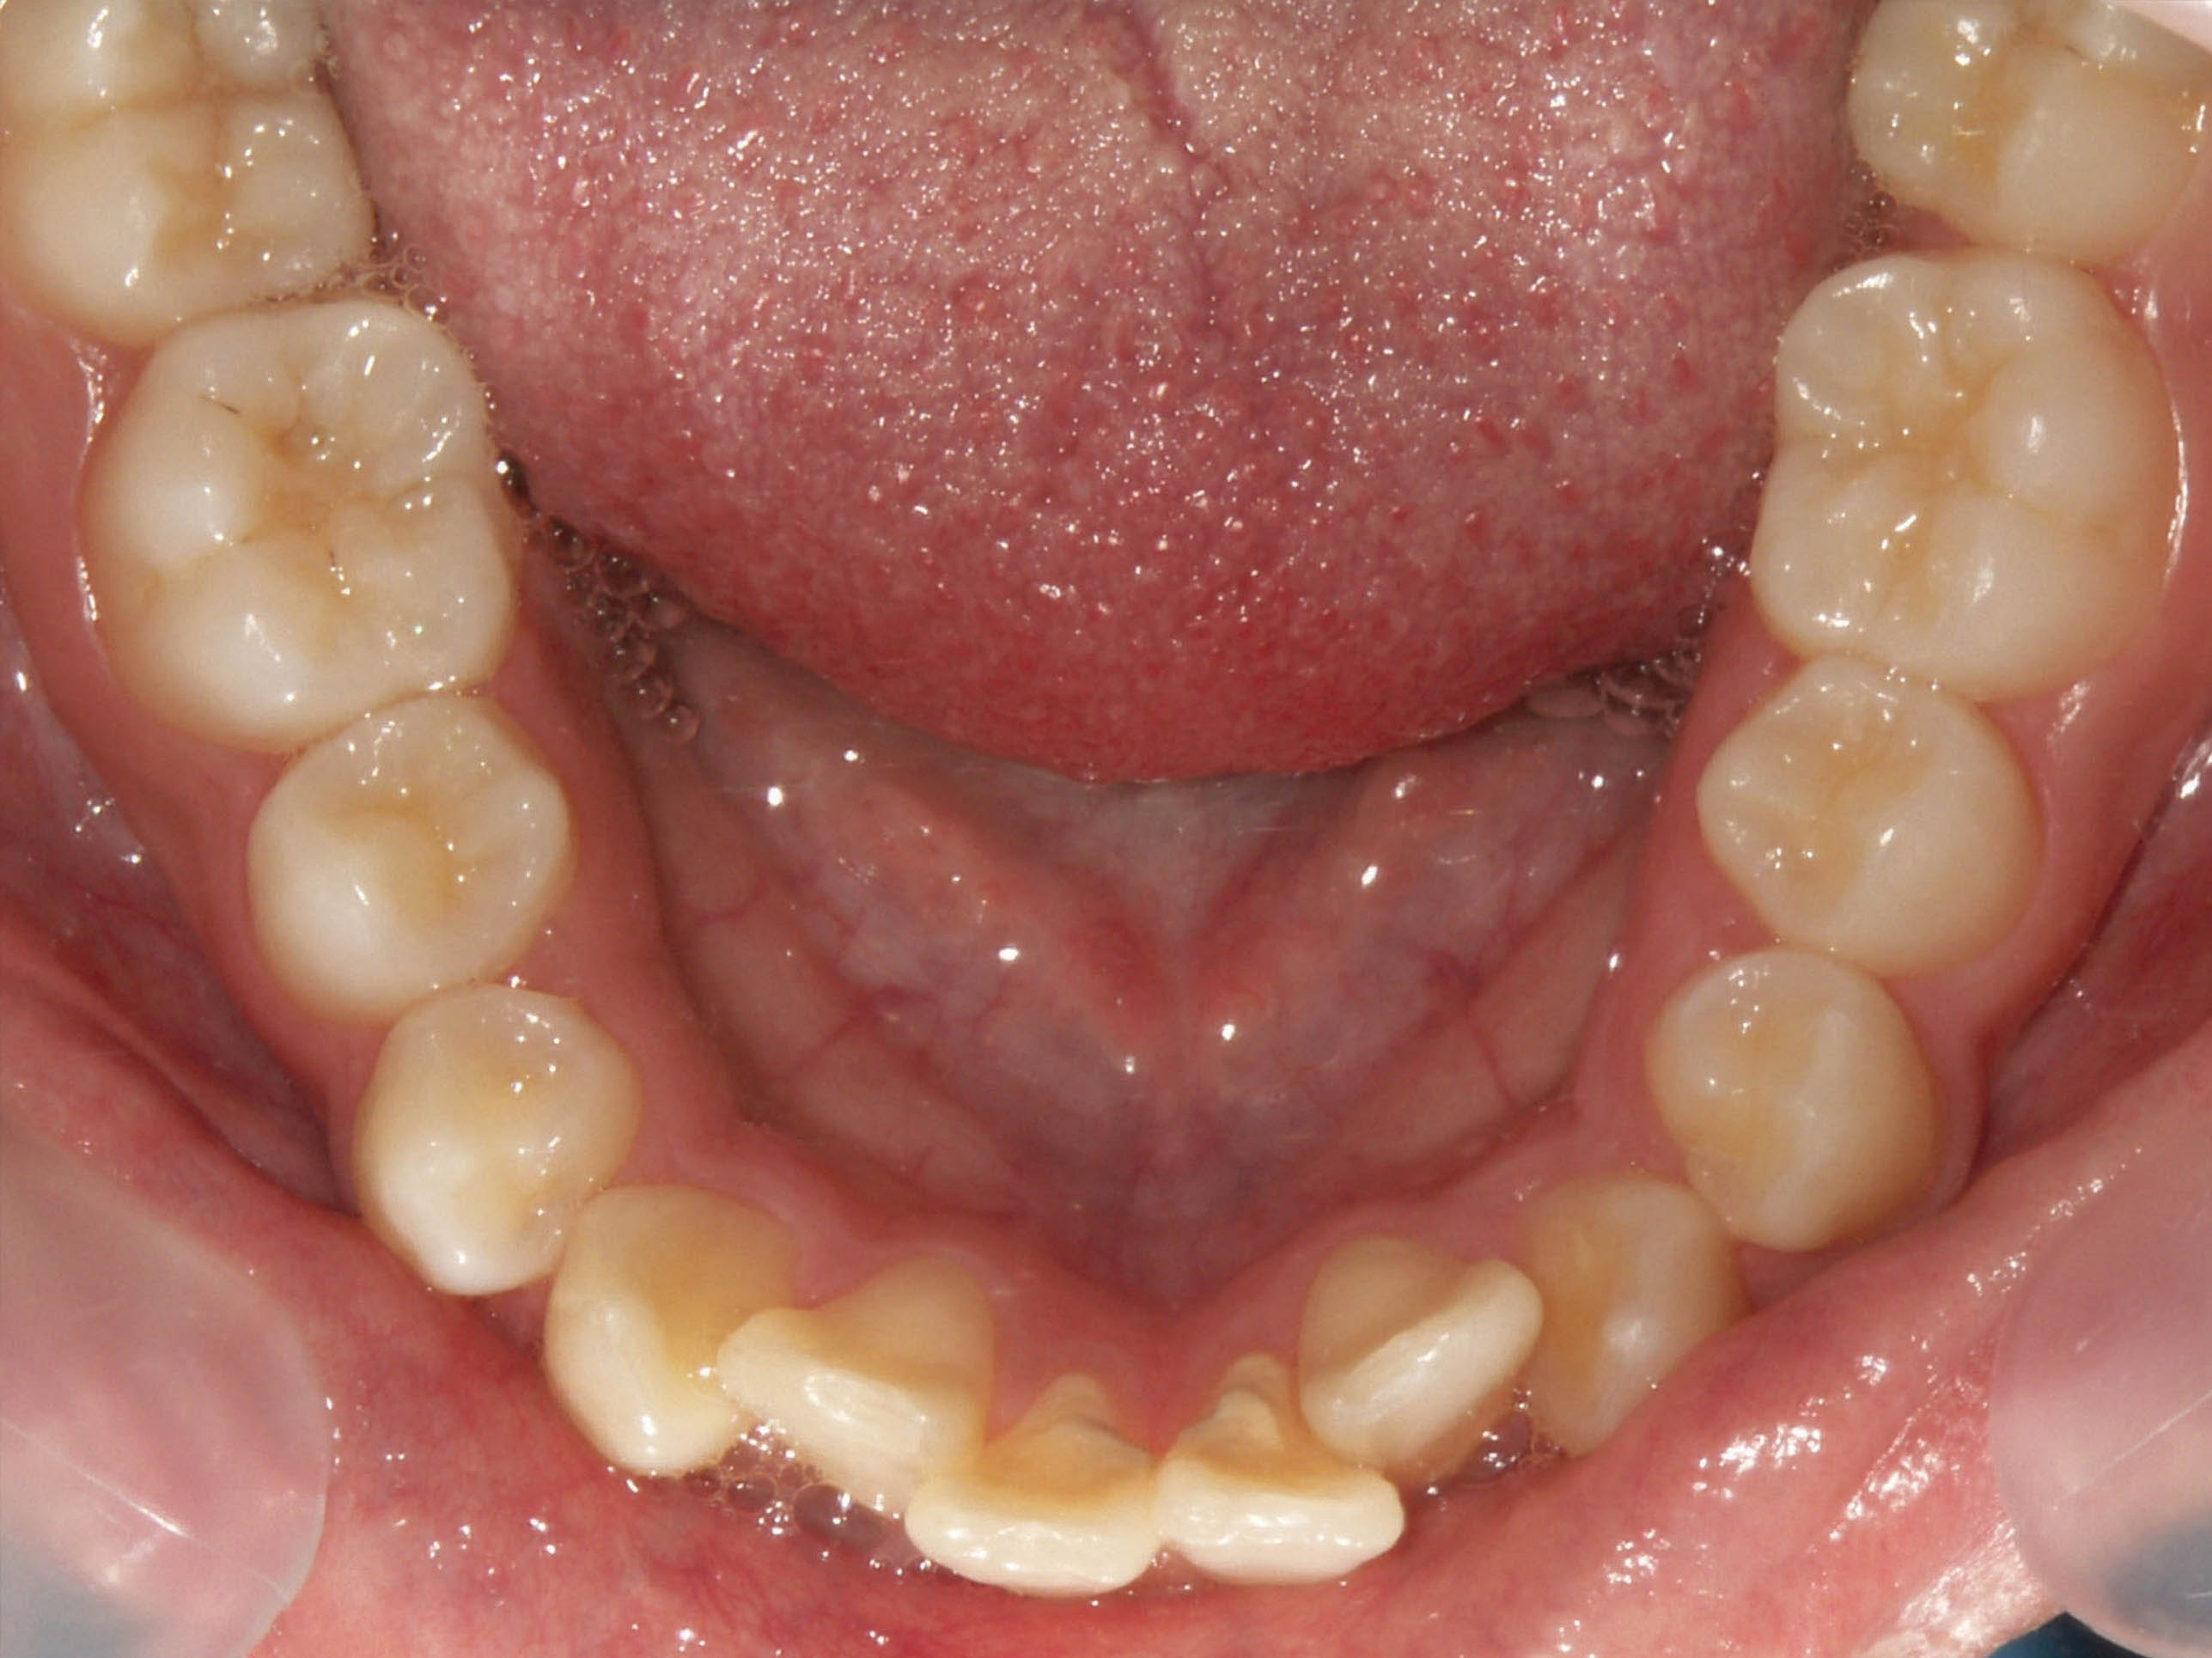

قبل از درمان